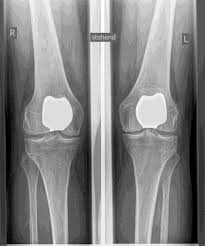

TKA (مفصل الركبة الاصطناعي)

يحل مفصل الركبة الاصطناعي محل سطح الغضروف الذي دمره التهاب المفاصل العظمي. يظل العظم الأساسي في عظم الفخذ والرأس الظنبوبي سليمًا. يقارن البعض مفصل الركبة الاصطناعي الحديث بتتويج الأسنان؛ والمصطلح الدقيق هو ما يسمى بإعادة تسطيح اللقمتين. بين الأسطح الجديدة في الجزء العلوي والسفلي من الساق يوجد ما يسمى بالبطانة المصنوعة من البلاستيك الأبيض المقوى خصيصًا، والتي يمكن رؤيتها في صورة الأشعة السينية على أنها المسافة بين الأجزاء المعدنية.